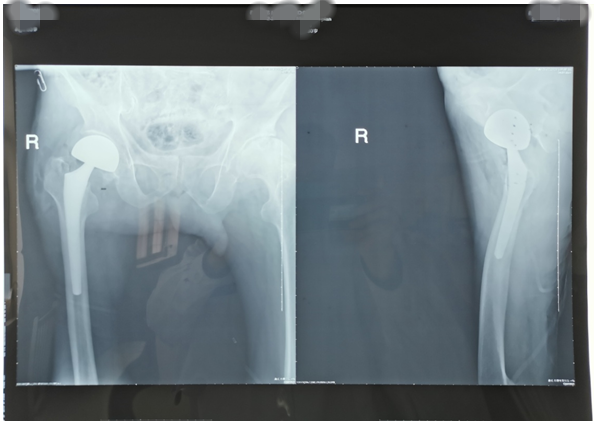

近期,我科又為兩位高齡老人因股骨頸骨折行髖關節(jié)置換術。一位是呂大爺,82歲高齡,右髖部外傷后疼痛一個月就診。當時呂大爺外傷后局部疼痛,未引起注意仍日?;顒?,癥狀逐漸加重后就診,既往有高血壓、腦梗塞、腦出血病史,入院后積極完善術前評估,在無絕對手術禁忌癥時行右側股骨頸骨折髖置換術,手術時間短,出血少,術后第二天呂大爺扶助步器下床活動,避免了因骨折長時間臥床各種并發(fā)癥的發(fā)生,老人及家屬對我們的治療非常滿意。(見下圖)

右髖正側位手術前后對比圖